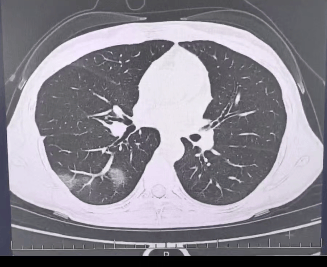

检查结果显示合约,

程女士的好几叶肺

都出现了“白肺”现象合约,

指间血氧饱和度只有 88%合约,

血心肌酶谱、肌钙蛋白的指标、肝功能的指标

也出现了明显的异常合约。

确诊流感(重型)合约!

图源:杭州市第三人民医院微信公众号